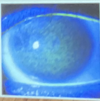

Que son los nódulos de Horner-trantas

Solo aparecen en conjuntivitis alérgicas graves